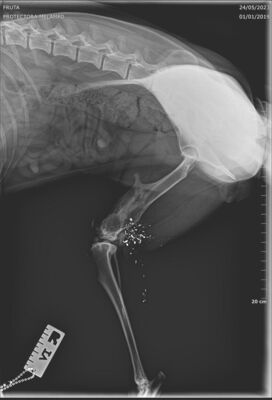

Update 26.05.2023

Fruta wurde kastriert und ihr alte Verletzung wurde dabei auch gleich geröngt. Dabei kam heraus, dass Fruta eine Schussverletzung hat und immer noch Schrot im Bein hat. Die Röntgenbilder sind weiter unten zu finden.

Fruta’s Hinterbein wurde beim Spezialisten abgeklärt. Das Bein ist steif, sie hat aber keine Schmerzen. Es stört sie auch nicht, sie läuft, rennt und hüpft auch ohne Probleme aufs Sofa.